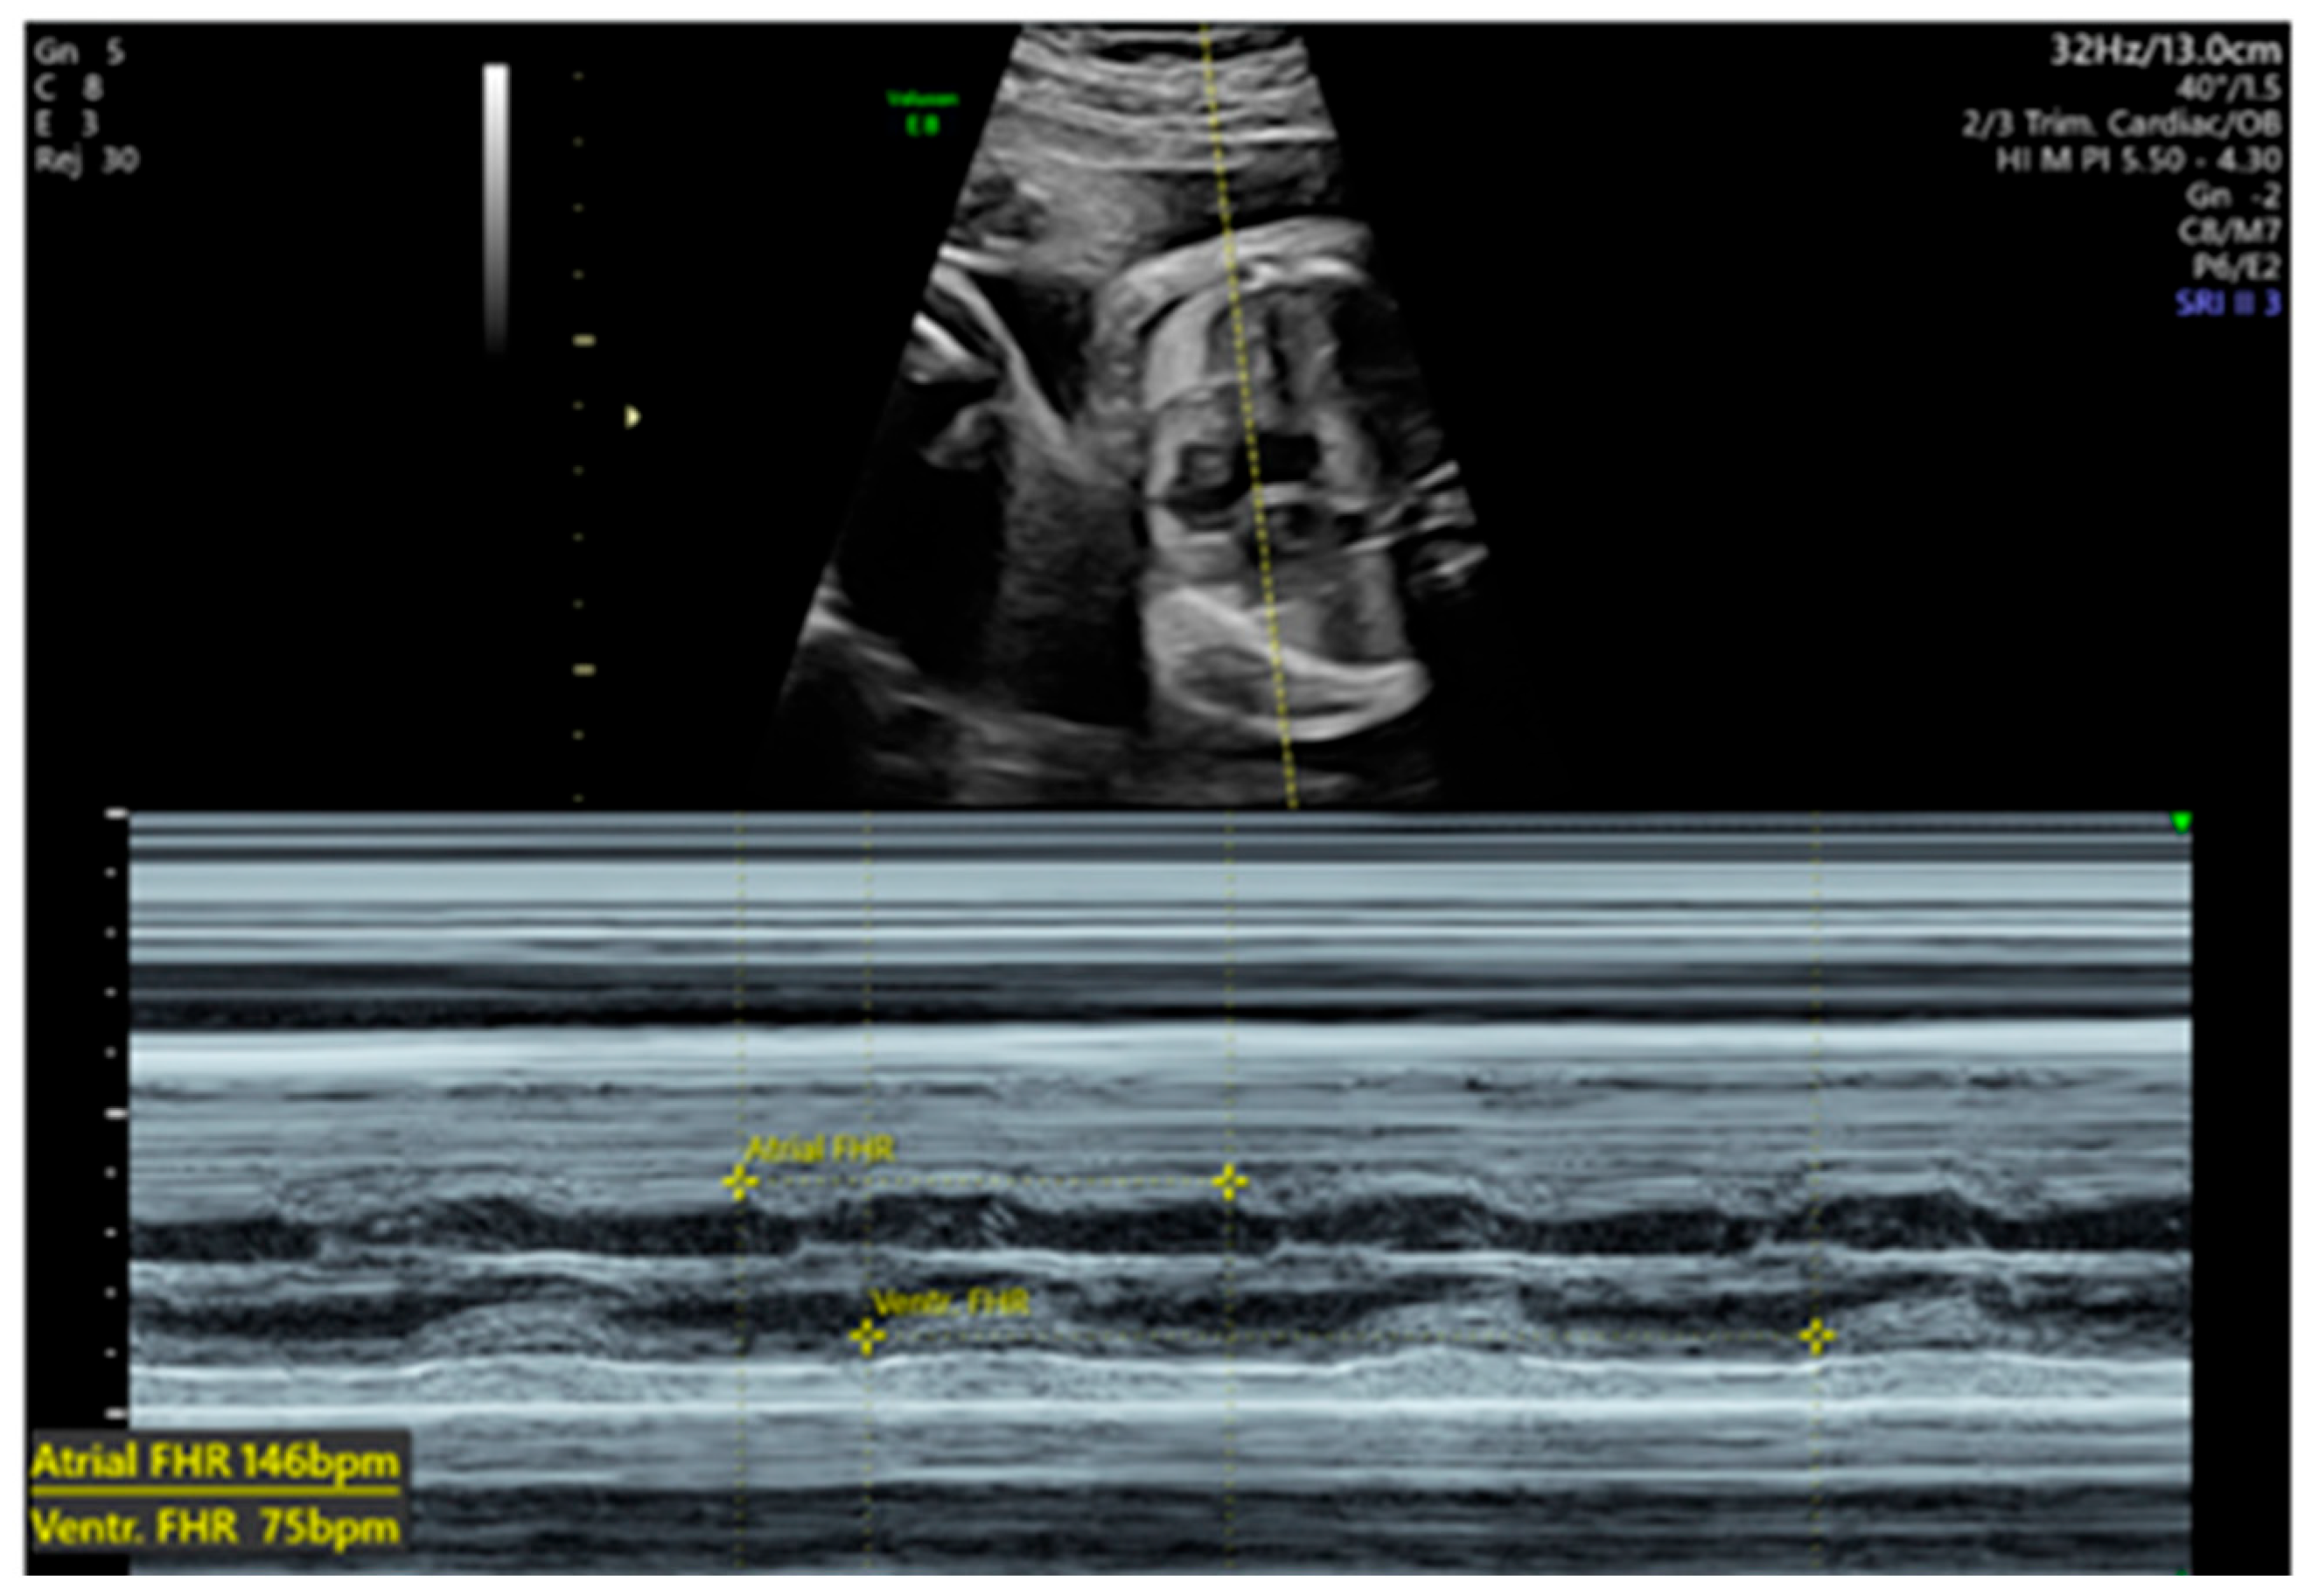

| 28 + 0 | First IVIG cycle (65 g total) | 75 | SF increased to 52%; mild improvement in contractility | Initiated due to signs of fibroelastosis |

| 31 + 2 | Post-IVIG peak response | 70 | SF: 59% (LV), 52% (RV); marked biventricular improvement | Aortic isthmus 3 mm (Z-score –1.65) |